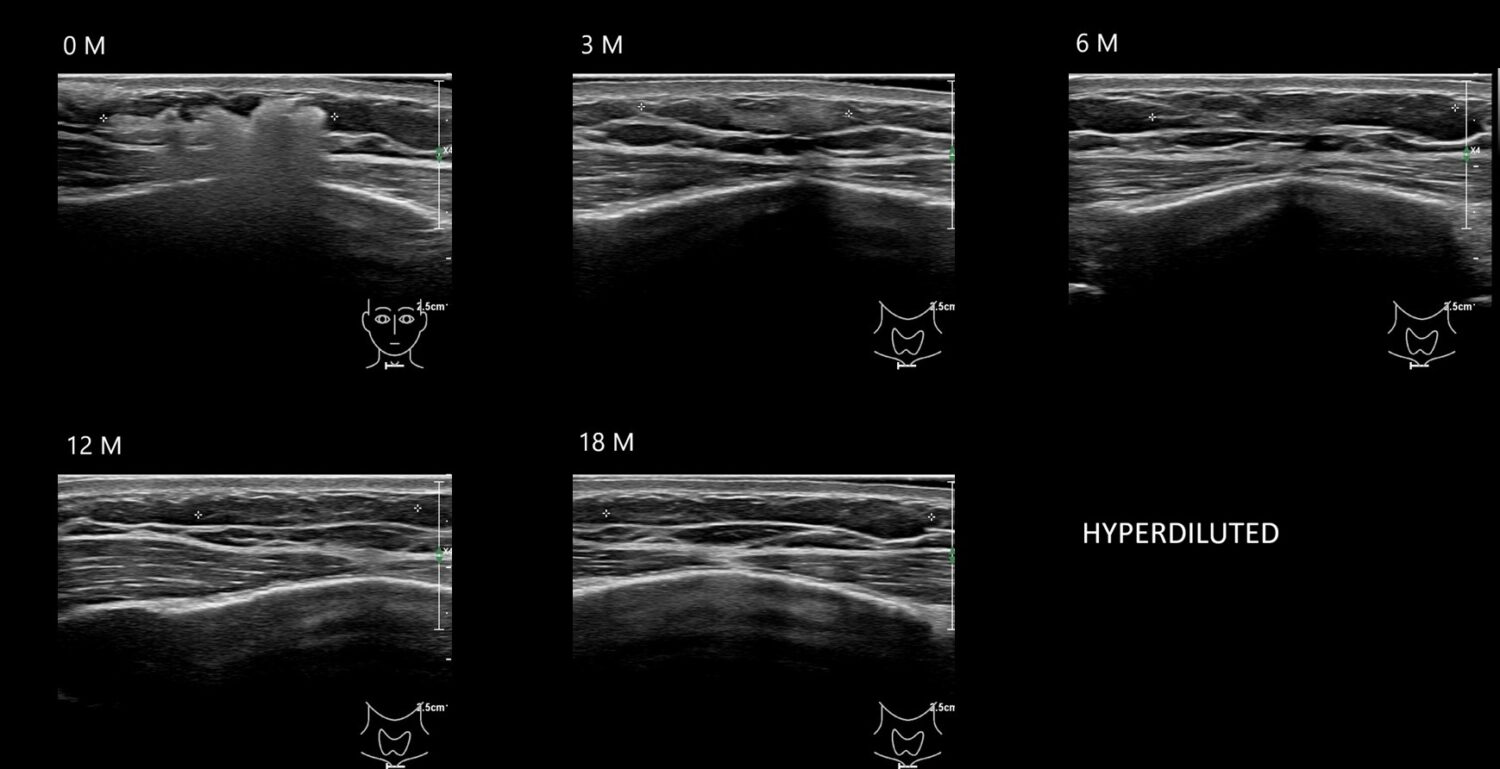

caha0